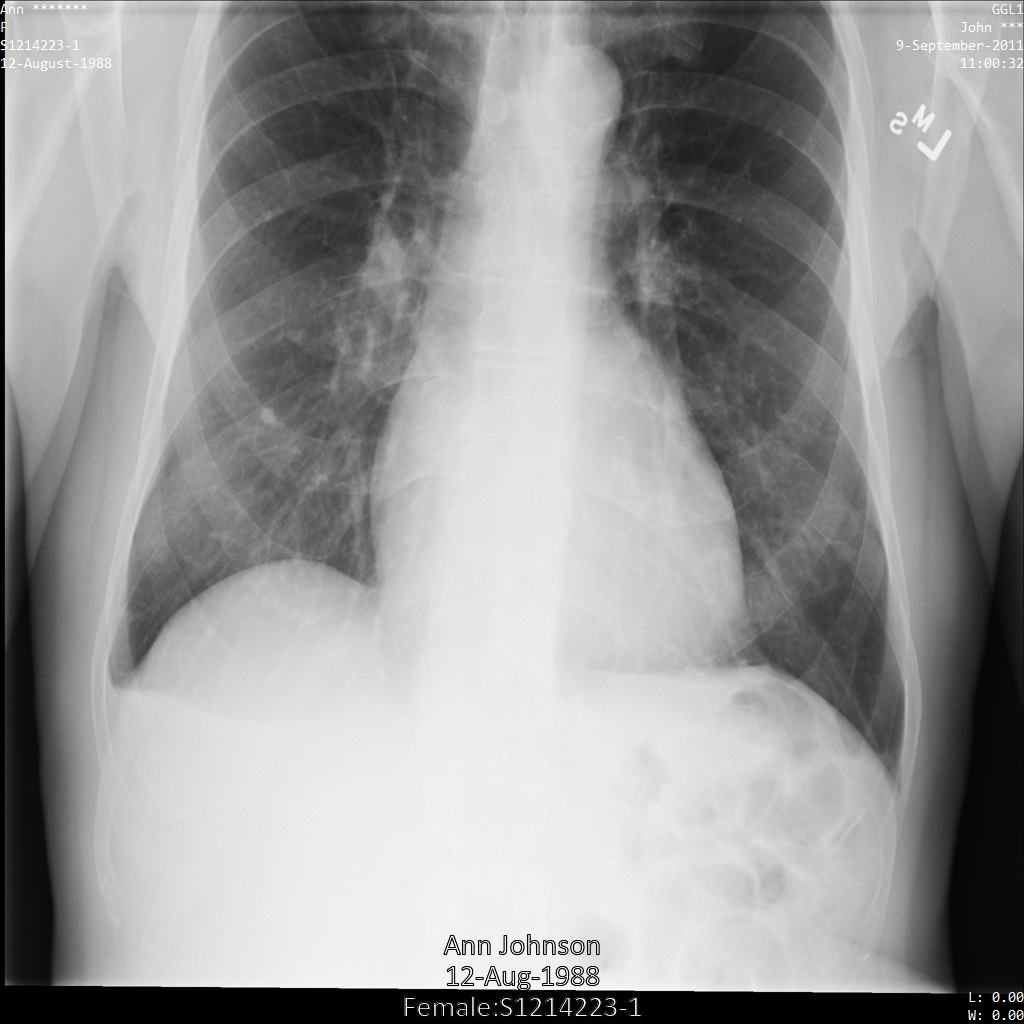

Ciascuna delle sezioni seguenti fornisce esempi di come anonimizzare i dati DICOM utilizzando vari metodi. Con ogni campione viene fornito un output dell'immagine deidentificata. Ogni campione utilizza la seguente immagine originale come input:

Puoi confrontare l'immagine di output di ogni operazione di deidentificazione con l'immagine originale per vedere gli effetti dell'operazione.

Dopo aver inviato l'immagine all'API Cloud Healthcare, l'immagine viene visualizzata come segue. Sebbene i metadati visualizzati negli angoli superiori dell'immagine siano stati oscurati, le informazioni sanitarie protette (PHI) incorporate nella parte inferiore dell'immagine rimangono. Per rimuovere anche il testo integrato, consulta Oscuramento del testo integrato nelle immagini.

Dopo aver inviato l'immagine all'API Cloud Healthcare, l'immagine viene visualizzata

come segue. Dei tag forniti nell'elenco di rimozione, solo PatientBirthDate

viene rimosso nell'immagine, in quanto è l'unico tag dell'elenco di rimozione che

corrisponde ai metadati visibili nell'immagine.

Mentre il PatientBirthDate nell'angolo in alto dell'immagine è stato oscurato in base alla configurazione nell'elenco di rimozione, le PHI personali incorporate nella parte inferiore dell'immagine rimangono. Per rimuovere anche

il testo integrato, consulta Oscuramento del testo integrato nelle immagini.

Dopo aver inviato l'immagine all'API Cloud Healthcare utilizzando il

profilo di filtro dei tag ATTRIBUTE_CONFIDENTIALITY_BASIC_PROFILE, l'immagine viene visualizzata

come segue. Sebbene i metadati visualizzati negli angoli superiori dell'immagine

siano stati oscurati, le informazioni sanitarie personali incorporate nella parte inferiore dell'immagine rimangono.

Per rimuovere anche il testo integrato, consulta

Oscuramento del testo integrato nelle immagini.

Dopo aver inviato l'immagine all'API Cloud Healthcare utilizzando

l'opzione REDACT_ALL_TEXT, l'immagine

viene visualizzata come segue. Il testo incorporato nella parte inferiore

dell'immagine è stato rimosso, ma i metadati negli angoli superiori dell'immagine

sono rimasti. Per rimuovere anche i metadati, consulta Anonimizzazione dei tag DICOM.

L'immagine seguente mostra una radiografia non oscurata di un paziente:

Dopo aver inviato l'immagine all'API Cloud Healthcare utilizzando le opzioni

REDACT_ALL_TEXT e DEIDENTIFY_TAG_CONTENTS, l'immagine viene visualizzata

come segue. Osserva le seguenti modifiche:

- I nomi nell'angolo in alto a sinistra e in alto a destra dell'immagine sono stati trasformati

utilizzando un

CryptoHashConfig - Le date nell'angolo in alto a sinistra e in alto a destra dell'immagine sono state trasformate

utilizzando un

DateShiftConfig - Il testo integrato nella parte inferiore dell'immagine viene oscurato

Dopo aver inviato l'immagine all'API Cloud Healthcare utilizzando il profilo DEIDENTIFY_TAG_CONTENTS, l'immagine viene visualizzata come segue.

Osserva le seguenti modifiche:

- I nomi nell'angolo in alto a sinistra e in alto a destra dell'immagine sono stati trasformati

utilizzando un

CryptoHashConfig - Le date nell'angolo in alto a sinistra e in alto a destra dell'immagine sono state trasformate

utilizzando un

DateShiftConfig

Dopo aver inviato l'immagine all'API Cloud Healthcare utilizzando la trasformazione

redactConfig, l'immagine viene visualizzata come segue: